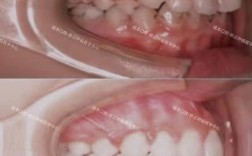

- 咬合调整:深覆合(上牙覆盖下牙过多)、深覆盖(龅牙)等问题开始改善。

- 嘴凸减轻:对于龅牙患者,嘴唇可能更自然贴合。

- 侧脸线条优化:下巴后缩或下巴前突的问题可能开始改善。